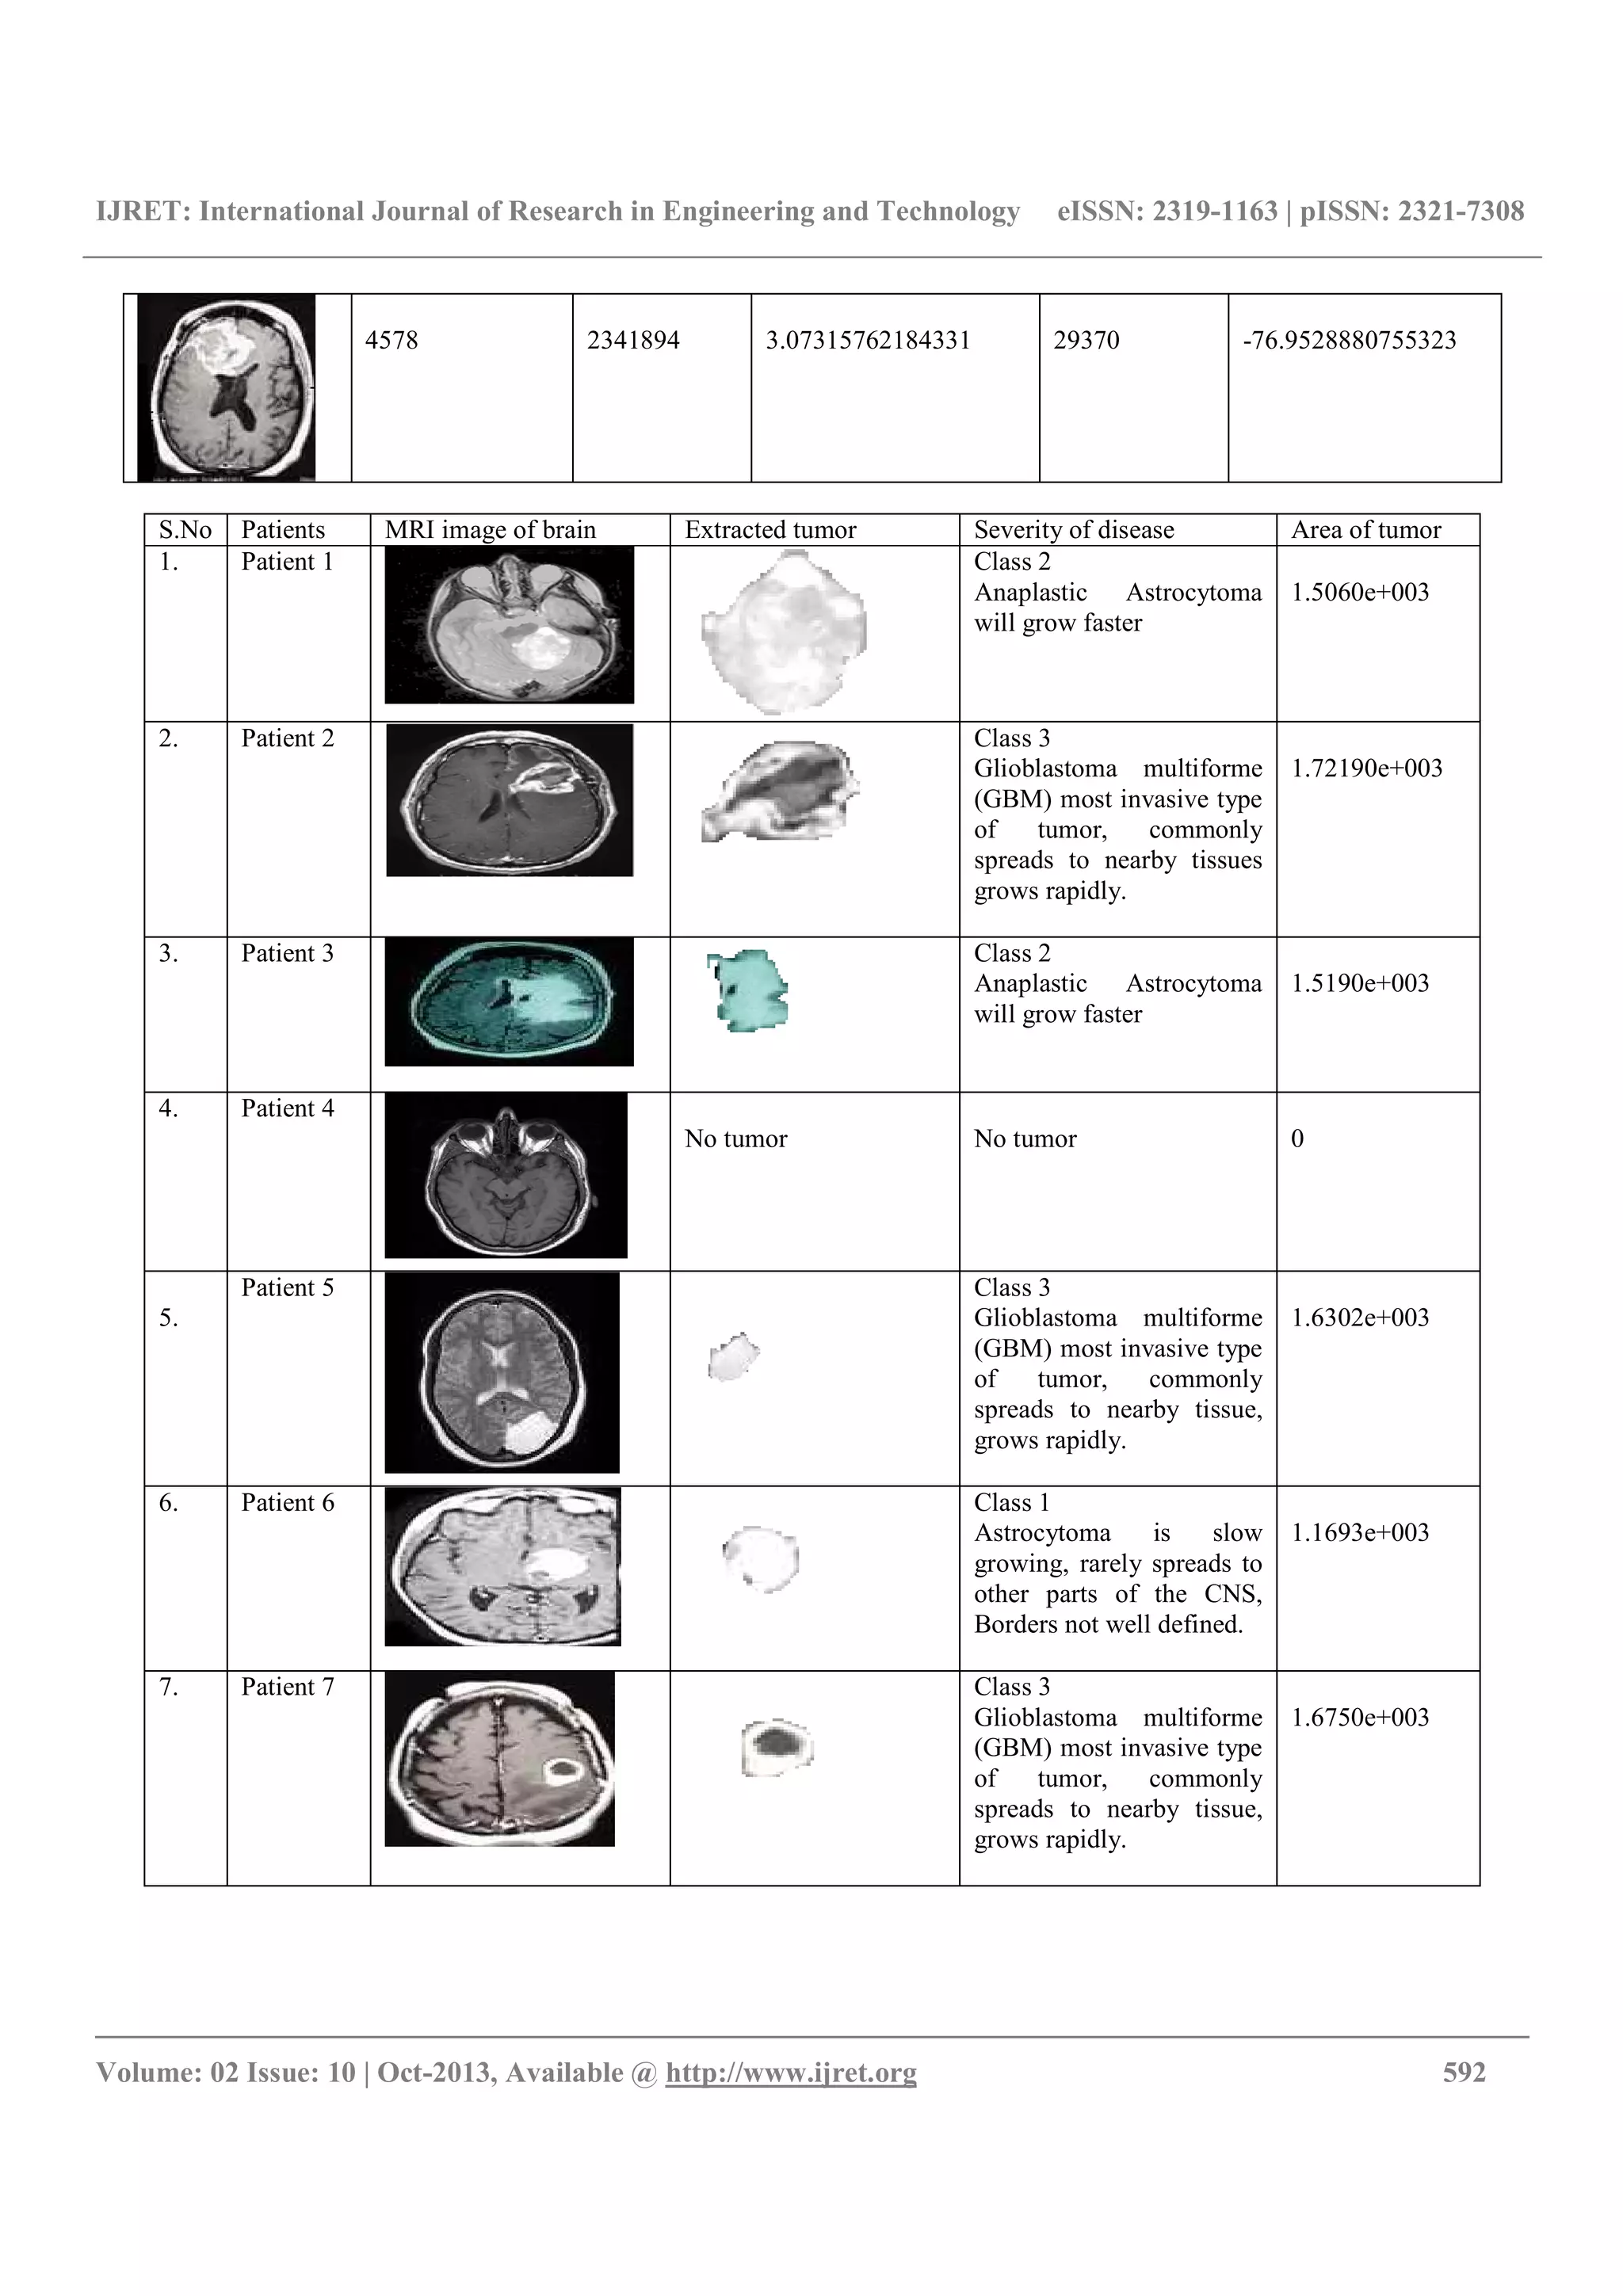

S.No Patients MRI image of brain Extracted tumor Severity of disease Area of tumor

1. Patient 1 Class 2

Anaplastic Astrocytoma

will grow faster

1.5060e+003

2. Patient 2 Class 3

Glioblastoma multiforme

(GBM) most invasive type

of tumor, commonly

spreads to nearby tissues

grows rapidly.

1.72190e+003

3. Patient 3 Class 2

1.5190e+003

4. Patient 4

No tumor No tumor 0

5.

Patient 5 Class 3

spreads to nearby tissue,

1.6302e+003

6. Patient 6 Class 1

Astrocytoma is slow

growing, rarely spreads to

other parts of the CNS,

Borders not well defined.

1.1693e+003

7. Patient 7 Class 3

1.6750e+003